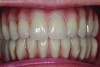

Patient intraoral condition 3 years following delivery of maxillary and mandibular All-on-4 denitive prosthesis.

Figure 20

Dental rehabilitation with the All-on-4 treatment concept is often a life-changing event for edentulous and terminal dentition patients that results in unprecedented quality of life improvements (Figure 17 through Figure 20).